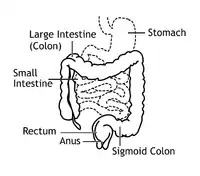

Large Intestine

The large intestine extends from the ileo-caecal junction to the recum and anus. The microscopic appearence is similar to that of the small intestine. In is divided into the caecum, ascending, transverse, descending and sigmoid colon. In the colon electrolytes and water are removed, and faeces are formed. These are propelled fowards by a form of movement called mass movement. (see Motility). The colon is populated with bacteria, which usually operate in a symbiotic mode. Any food that has not been processed may be digested by these bacteria, and the products will then be absorbed by the large intestine.

Rectum and Anus

The faeces are now passed to the rectum where they await elimination. The process of elimination is controlled by two sphinctae, the Internal and external anal sphinctae. The former is under involuntary control, the latter under voluntary control. The functioning of these are discussed in the section on Motility